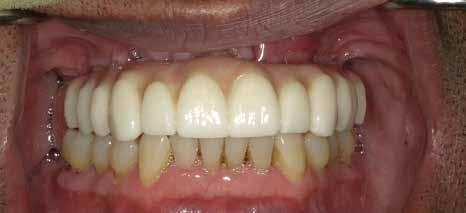

72 FDC 2026 Speaker: Full Arch Implant Reconstruction in the Digital Era: Past, Present and Future